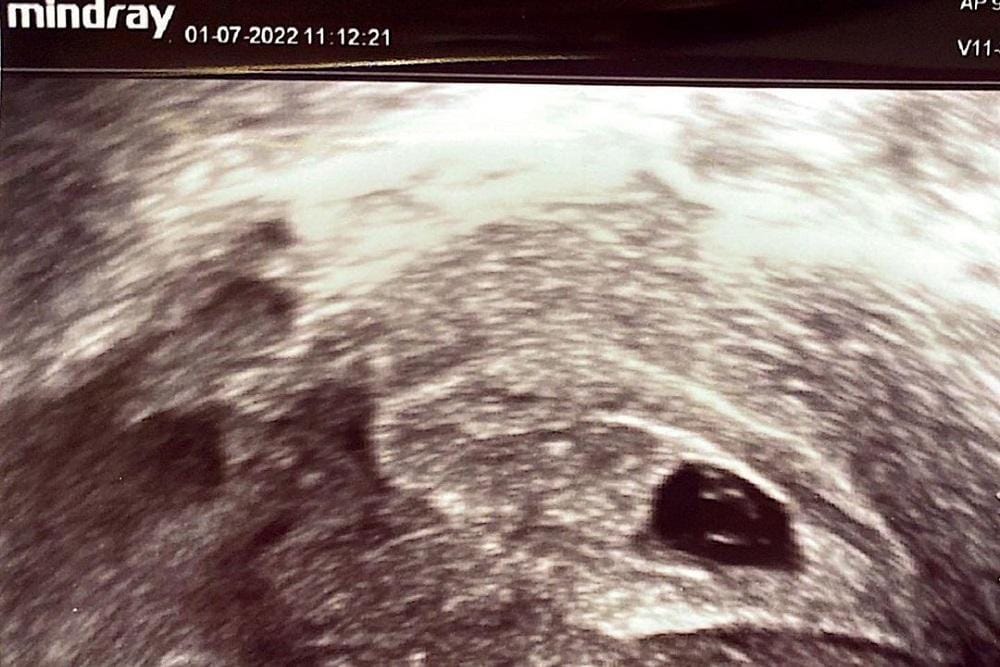

Berita bahagia itu tidak berlangsung lama. Dokter menyatakan kehamilan Annisa Pohan bermasalah. Janin yang sedang dikandungnya tidak berkembang di usia 7 minggu.

“Namun qadarullah, mungkin Allah punya rencana lain yang lebih baik. Kehamilan saya dinyatakan tidak berkembang di usia 7 minggu, ukuran baby-nya terlalu kecil dan tidak ada detak jantungnya, sehingga tidak dapat dipertahankan,” tulis Annisa.